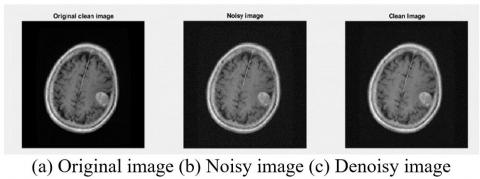

In this section, three image samples were used to illustrate the noise removal results as the first preprocessing step (Figure 7-9).

Figure 7. NLM filter results with Gaussian noise standard deviation 5

Figure 8. NLM filter results with Gaussian noise standard deviation 5

Figure 9. NLM filter results with Gaussian noise standard deviation 5

As can be seen in Figures 7-9, the image quality was improved after noise removal.

Also, despite noise removal, the edges still have more detail than other noise removal methods.

Among the advantages of these non-local filters are the desired quality and quantitative results in a variety of images, especially textured and duplicate ones. That's why we've tried to use this method for pre-processing to help improve noise elimination. Table 3 examines the quantitative criteria for noise abatement.